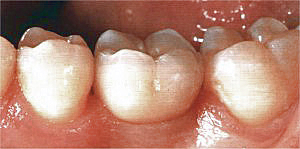

Die vom Zahntechniker hergestellte Krone.

Die einzementierte Krone fügt sich in Farbe und Form harmonisch in die bestehende Zahnreihe ein.